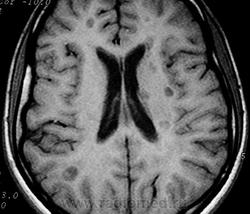

ГМ. Рассеянный склероз 3. +

Рассеянный склероз